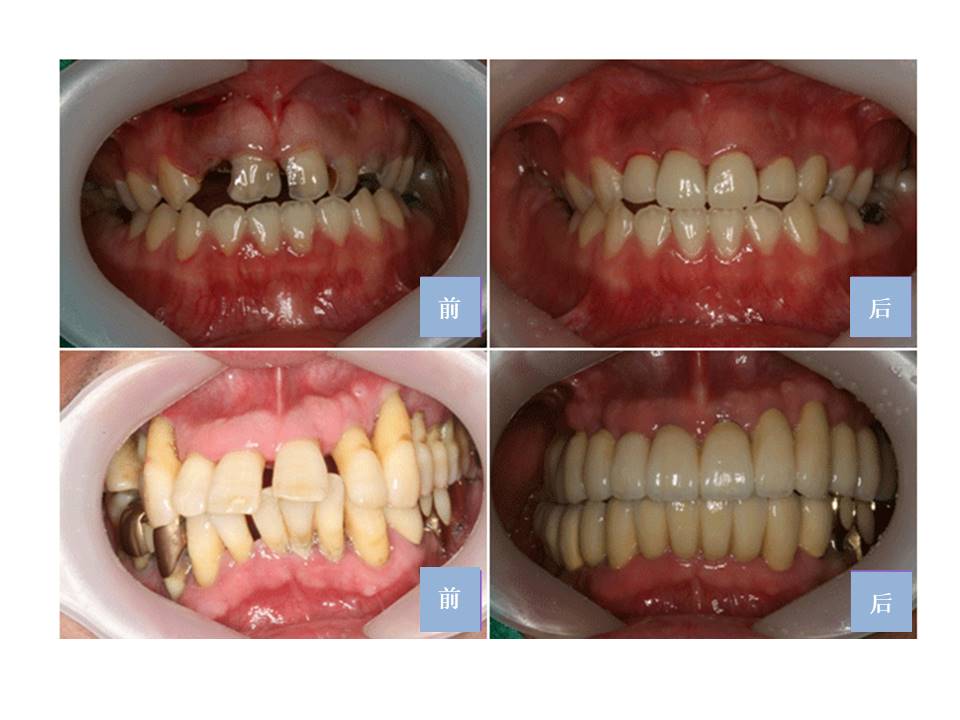

- 58对于不喜欢牙科的患者好消息! 睡眠种植牙是对于种植牙手术害怕,痛症,机械噪音等这种许多原因不能接受手术的患者开始的手术方式。睡觉的状态上没有痛症,害怕时接受种植牙手术的方式。跟全身麻醉不同有意识的状态上进行,非常平安的精神状态比较安全的手术方式后遗症也很少。最近普遍化的手术。 睡眠种植牙是通过静脉注射假睡眠状态上一些麻醉手术。这种睡眠种植牙手术是进行时几乎没有手术中的记忆,非常舒服所以可以说镇静麻醉。